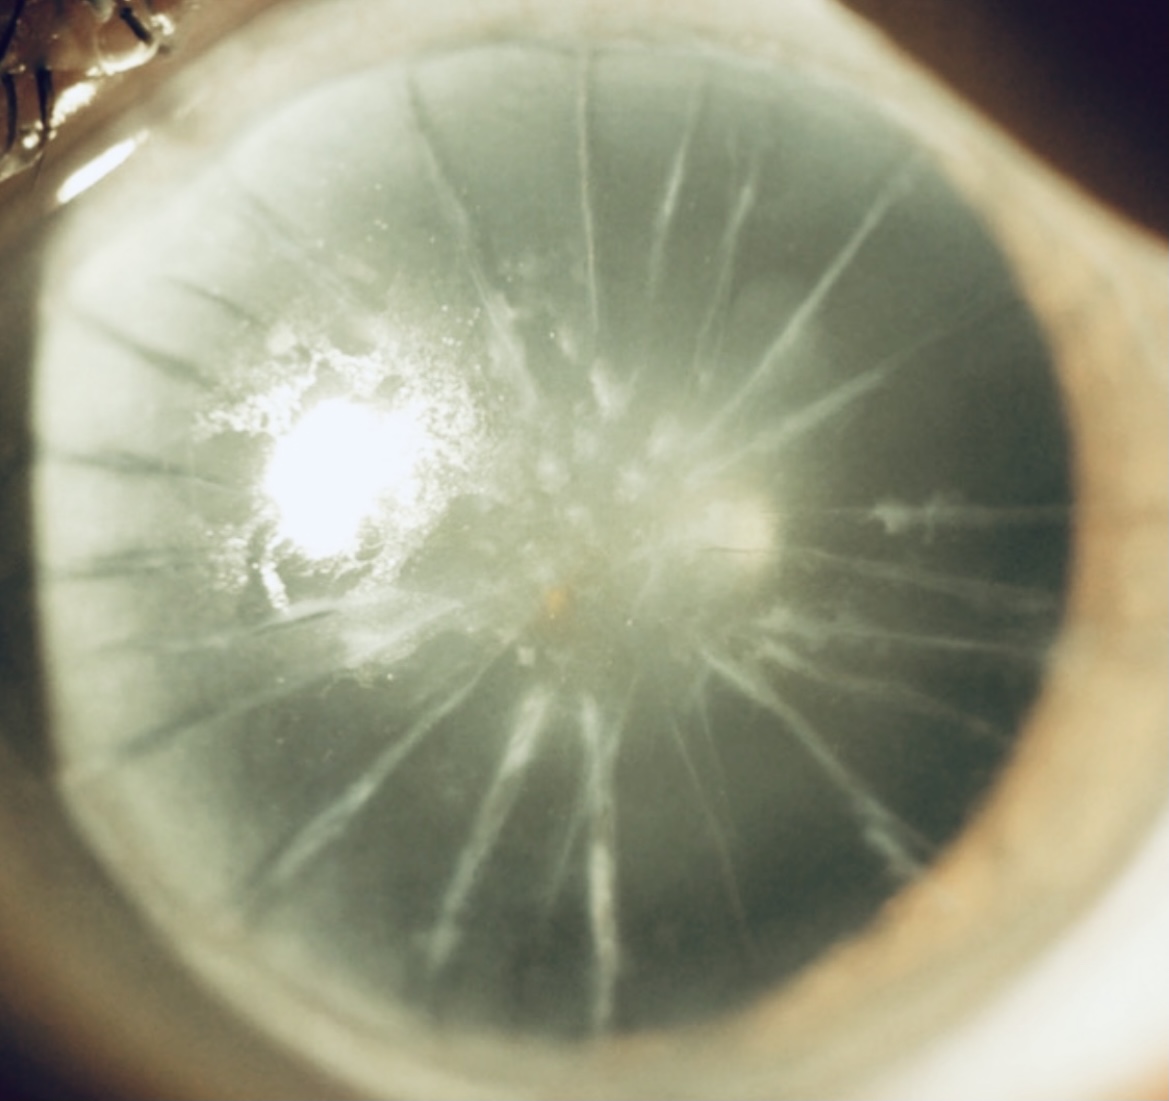

Radial Keratotomy (RK) Repair: World’s Best Cornea Specialist, Dr. Gulani for RK Correction in Minutes When “Impossible” Isn’t an Option In the world of modern refractive surgery, few cases test the limits of surgical artistry like Radial Keratotomy (RK). These are eyes etched decades ago with multiple corneal incisions—some as many as 32 to 40 […]